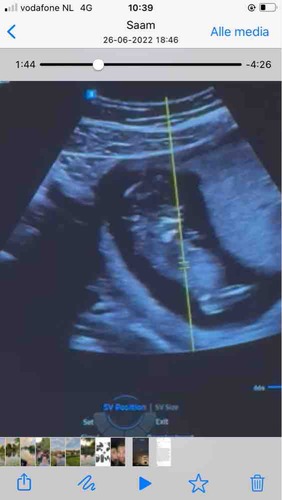

Jammergenoeg kan ik van de laatste echo ook de nub niet goed zien. En weet ook niet zeker of het de blaas is wat ik zie. Als je een filmpje hebt zou het mooi zijn als je een paar foto's maakt van stilstaand beeld. Maakt niet uit of het er meerdere zijn en of je toch wat van het beentje ziet zoals bij de vorige echo. Want soms lukt het met bewerken alles toch scherper en duidelijker te krijgen. Filmpjes kun je volgens mij nog steeds niet plaatsen in dit forum. Op het moment begin ik een beetje te neigen naar dat het een jongen in wording is. Maar moet daar toch wat meer dingen voor zien voor ik een gok neem.

Blauw: omranding

Rood: Blaas

Groen: stand nub en blaas met ruggengraad

Zoals je kan zien in de ingezoomde echos met alleen blauw zie je een klein bolletje/boven de nub lijn. Dit is normaal het begin van de ontwikkeling van de pipi

De lijn van de nub veranderd dan in de balletjes.

Zoals op de echo met de andere kleuren lijnen is er meer schaduw bij gedaan waardoor je ook duidelijker ziet dat de nub omhoog staat. De blaas zit ook erg laag en van nub naar blaas naar ruggengraad staat het in een hoek naar de ruggengraad(📐) dit duidt op een jongen. Bij meisjes loopt het gelijk of bijna gelijk aan de ruggengraad(=) de blaas zit daar dichter tegen de nub aan en is de nub plat en is er geen bolletje.

Dus ik gok jongen

Bedankt voor de uitgebreide uitleg.👌🏻 Ik ben 13+6.

Moet wel zeggen dat ik wel wat meer had verwacht met dat termijn. Vaak zie je dan al echt pipi en balletjes omhoog staan. Maar kan ook liggen aan hoe ze de echo gemaakt hebben. Bij een meisje met dit termijn moest het zowiezo plat zijn. Dus denk dat ze expres de echo wat minder duidelijk(donkerder) hebben gehouden bij de nub heb ik wel wat vaker gemerkt.

Maar door alle duideljke dingen gok ik toch echt jongen. Laat je het nog even weten als je het weet?